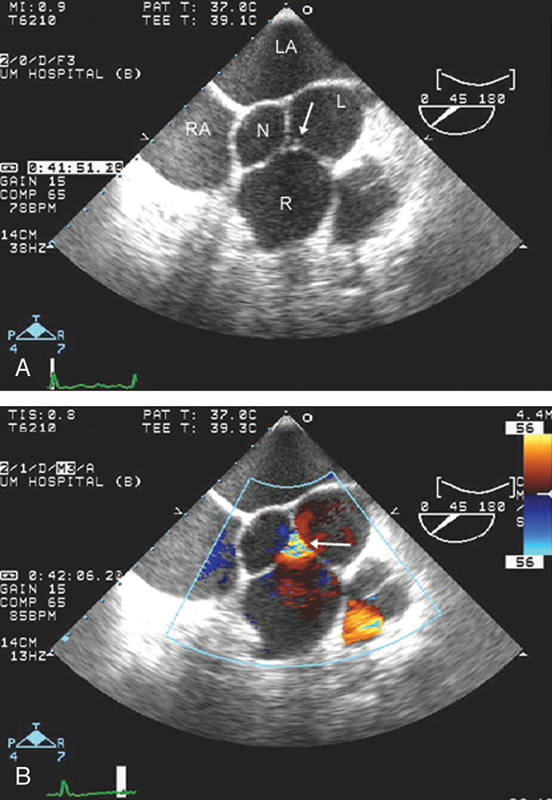

فحوصات تشخيصية لبعض امراض القلب والشرايين التاجية